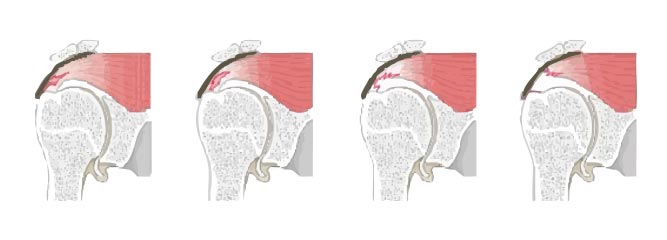

Erkrankungen und Verletzungen der Rotatorenmanschette: Ursachen, Ausprägungen und Behandlungsmöglichkeiten

Teilabriss der Rotatorenmanschette

1. Halbmondförmiger Abriss

2. V-förmiger Abriss

3. L-förmiger Abriss

4. U-förmiger Abriss